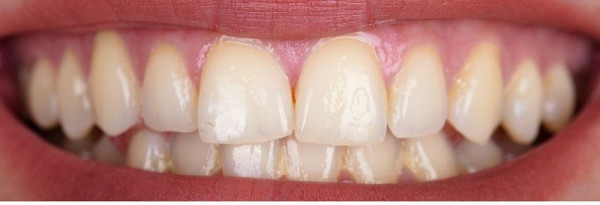

Radiant Transformations:

Before & After Gallery

Explore the captivating journey of patients who have experienced remarkable transformations, embracing newfound confidence and showcasing the true impact of our commitment to unparalleled dental excellence. Each image tells a story of not just aesthetic enhancement but also the restoration of joy and self-assurance.